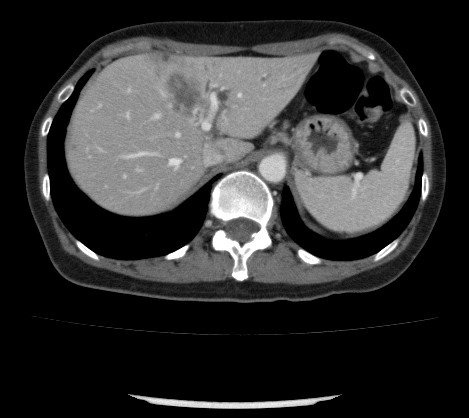

PVT diaqnozunu dəqiqləşdirmək üçün portoqrafiya aparılır – Doppler USM, KT və ya MRT angioqrafiya.

- Kontrastlı müayinələrdə damarda tromb və ya kavernoz transformasiya

- portoqrafiyada vena mənfəzində trombun görünməsi;

- venanın distalında genişlənmə və kavernoz transformasiyanın görünməsi;